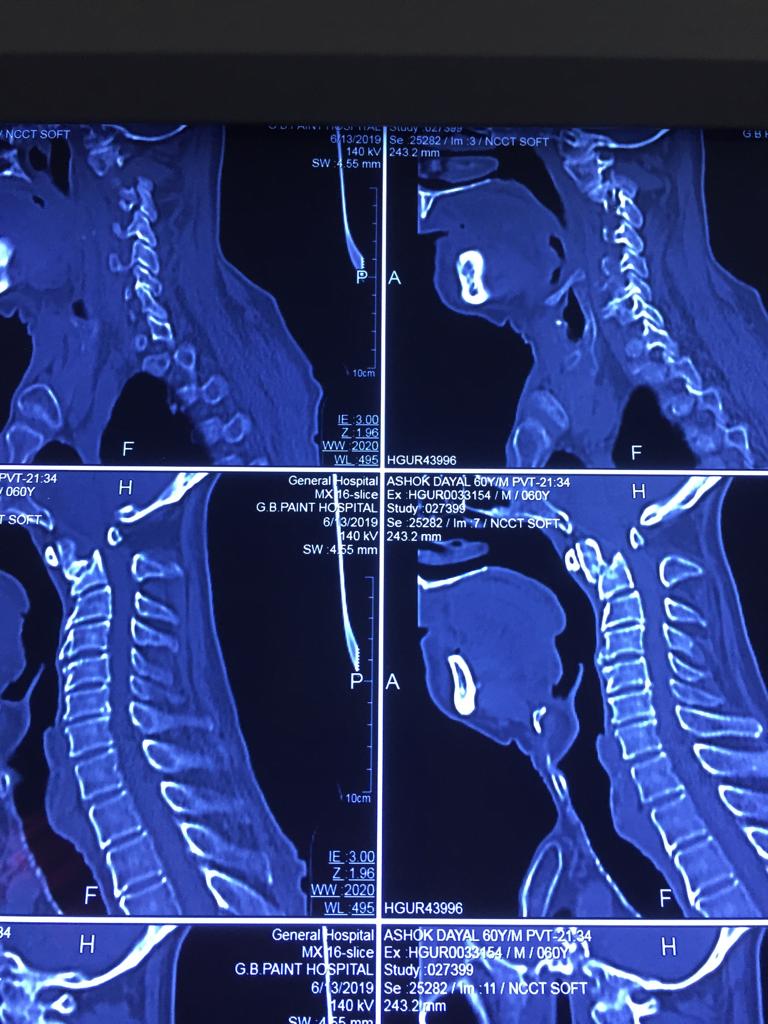

Cases